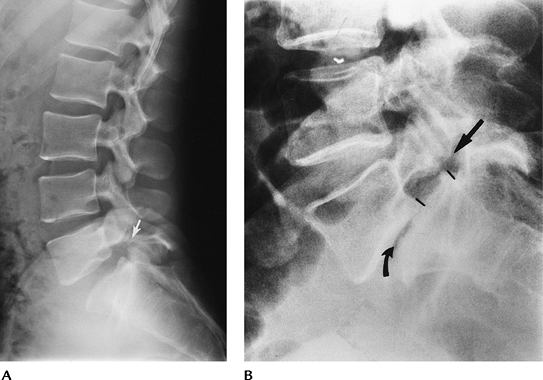

![]() |

FIGURE 3-39 Flexion (A) and extension (B)

radiographs of Grade 1–2 spondylolisthesis that increases with flexion. At this level, the subluxation is most commonly the result of facet degenerative disease. |

FIGURE 3-40 (A) Lateral radiograph demonstrating a pars defect at L5 (arrow) with slight subluxation of L5 on S1. (B) Lateral radiograph shows Grade 2–3 subluxation caused by a pars defect (arrow). There is associated degenerative disc disease (curved arrow).